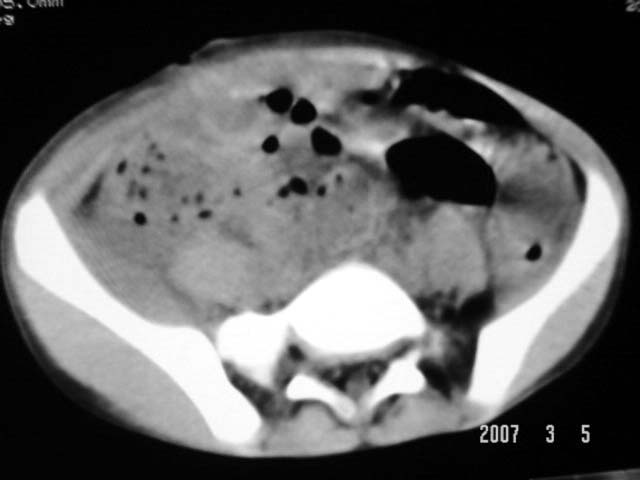

以下是引用dyqct在2007-3-5 10:28:00的发言:[br]右髂窝肿块。[br][br][br][br]